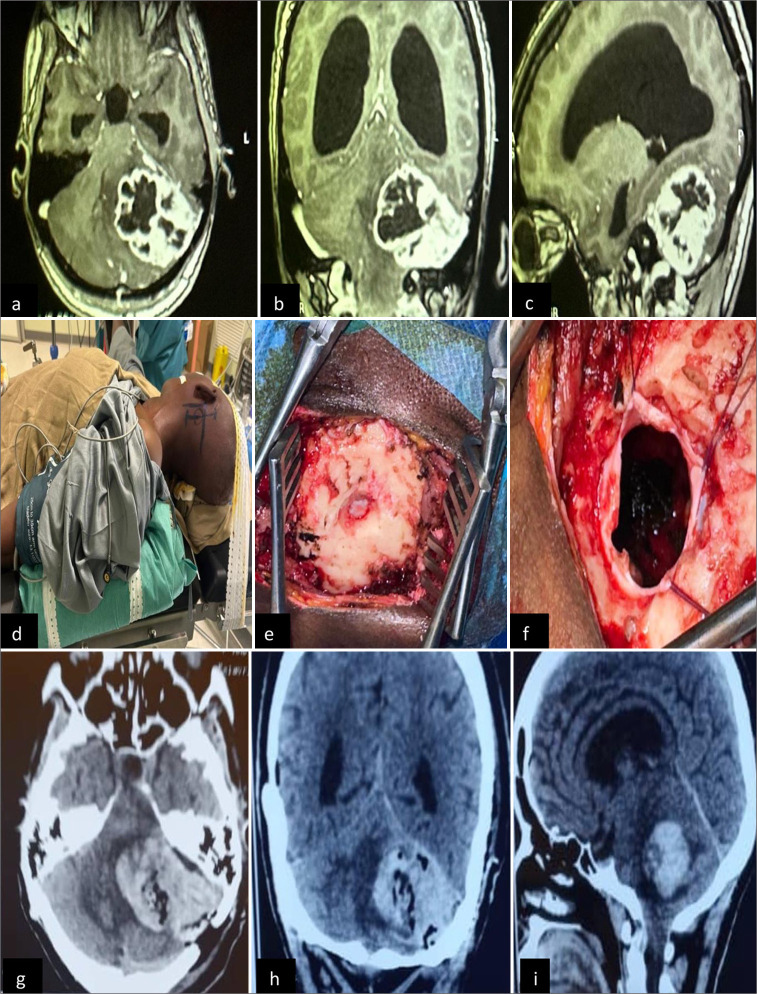

Background: There is a paucity of information regarding the surgical outcomes of brain tumors in sub-Saharan Africa. This study sought to address some of the existing gaps in knowledge concerning the epidemiology and management of brain tumors as well as postsurgical complications in Guinea, in comparison with the existing literature.

Methods: Three hundred seventy-four patients were diagnosed with brain tumors at the Department of Neurosurgery of a tertiary hospital in Conakry between July 2019 and June 2024. This retrospective study included patients who underwent surgical intervention in our operating room with at least one complication occurring within 30 days of surgery.

Results: Sixty-five patients were included in this analysis, with a predominance of the 25-55 age subgroup and a male: female ratio of 37:28. Over 50% of the patients presented with a diagnostic delay of more than 3 months, and 73% underwent surgery with a further delay of more than 1 month. Of the patients, 76.9% had a World Health Organization score of ≥2, and 25% underwent emergency surgery. Gross total resection was performed in 41% of the cases, and 44.6% of the patients underwent surgery for more than 4 h. A total of 27 patients (41.5%) developed 32 complications including 10.7% neurological deterioration, 21.5% regional complications, and 9.2% systemic complications. Eleven patients died, seven patients recovered, and 19 patients remained in a stationary state, giving an overall rate of 67.2% favorable outcomes.

Conclusion: These findings underscore the need for continued investment in the neurosurgical infrastructure, training, and technology to improve outcomes and reduce complications.